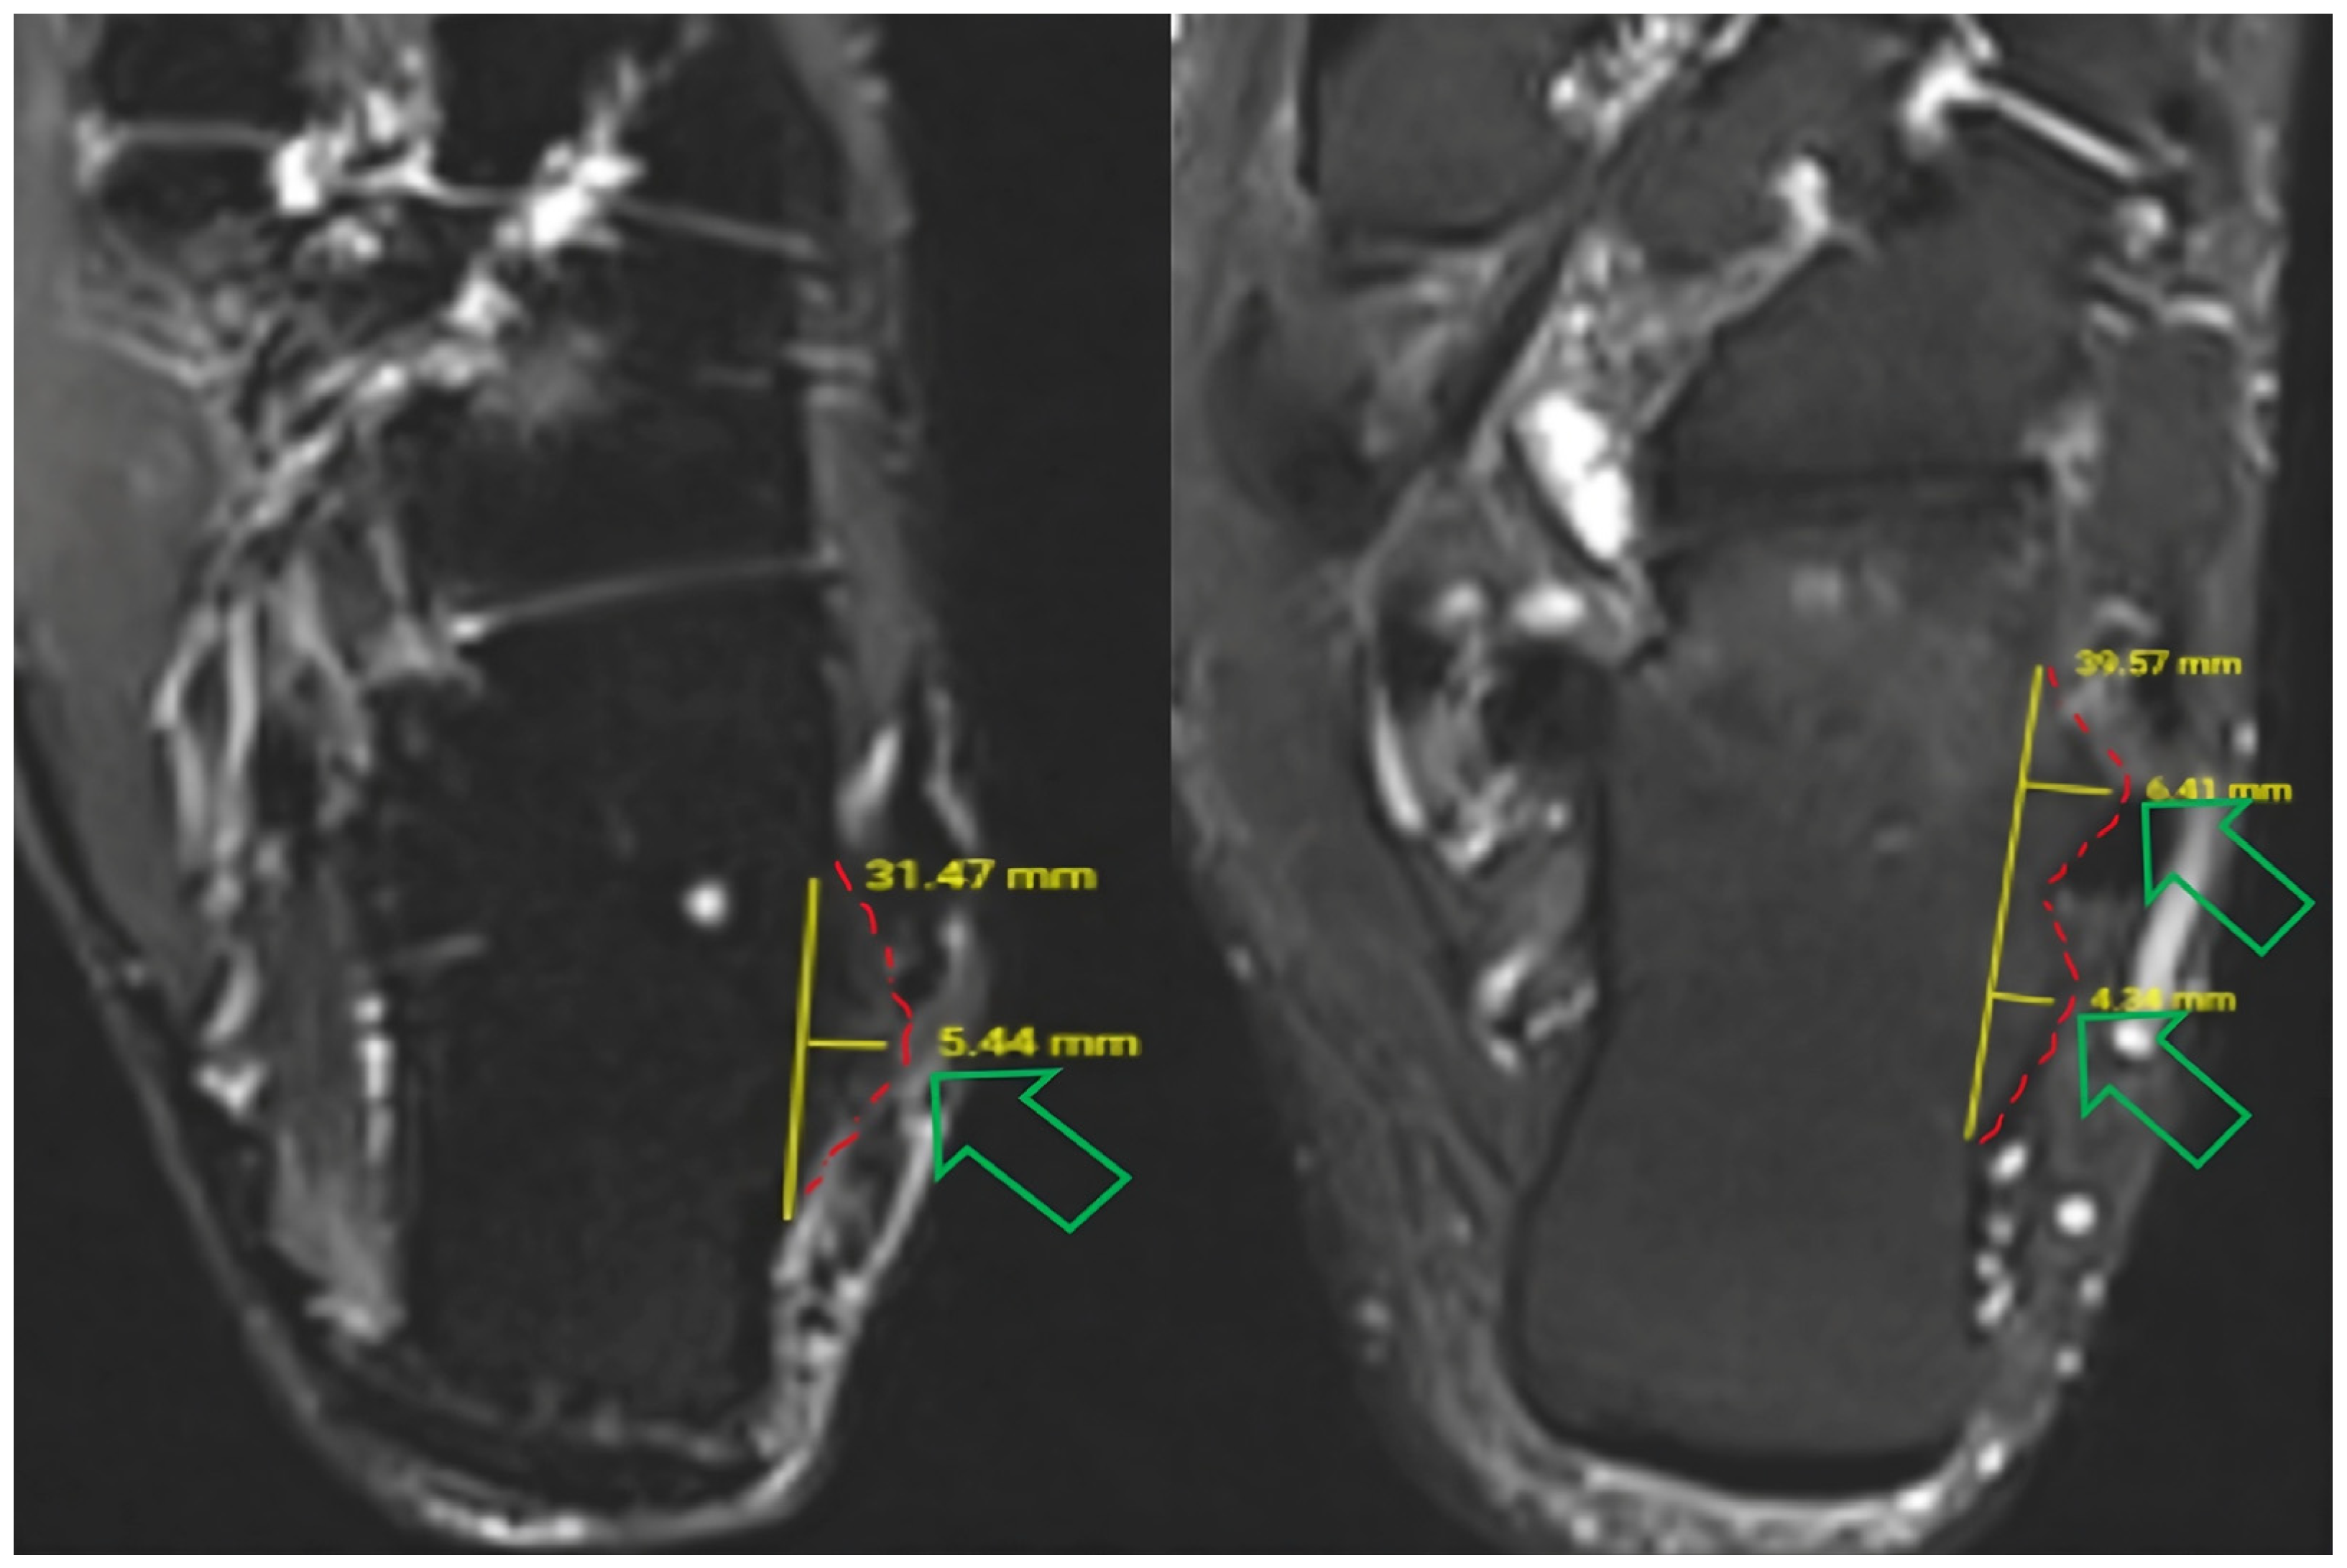

2.4.1. Peroneal Tubercle Morphology

Peroneal tubercle morphology was classified according to the framework described by Vosoughi and Tabatabaei [10]. For operational consistency on axial images, single-convex morphology was defined as a single distinct convex bony prominence along the lateral calcaneal wall. Double-convex morphology was defined as two adjacent convex prominences (anterior and posterior peaks) separated by a relative concavity/groove on the same axial level (Figure 2). In this cohort, an identifiable peroneal tubercle was present on axial MRI in all included examinations; therefore, no cases were excluded due to tubercle absence.

2.4.2. Peroneal Tubercle Height Measurement

Peroneal tubercle height was measured on axial images at the level of maximal tubercle prominence, defined as the slice demonstrating the greatest protrusion from the lateral calcaneal cortex. A reference line was drawn tangential to the lateral calcaneal surface, and height was recorded as the maximum perpendicular distance from this line to the tubercle apex. Measurements were performed on both axial T1- and T2-weighted sequences when available, and the mean value was used for analysis (Figure 2). For double-convex tubercles, height was defined as the maximum perpendicular distance to the higher of the two peaks on the same axial slice.

2.4.3. Peroneal Tubercle Length Measurement

Peroneal tubercle length (anteroposterior footprint) was measured on the same axial slice used for height measurement (maximal tubercle prominence). Length was defined as the maximal anteroposterior distance between the most anterior and most posterior cortical margins of the tubercle at its base along the lateral calcaneal wall (Figure 2). Measurements were performed using the PACS digital caliper tool with identical window/level settings, and the recorded value was used for descriptive and exploratory analyses.

Figure 2. Axial MRI examples demonstrating peroneal tubercle height and anteroposterior length measurements (yellow lines) at the level of maximal prominence and the classification of single-convex (left) and double-convex (right) morphologies. The green hollow arrow on the left indicates the apex of a single-convex peroneal tubercle, while the two on the right indicate the apices of a double-convex peroneal tubercle morphology. The red dashed lines mark the upper boundary of the tubercles on both the right and left.